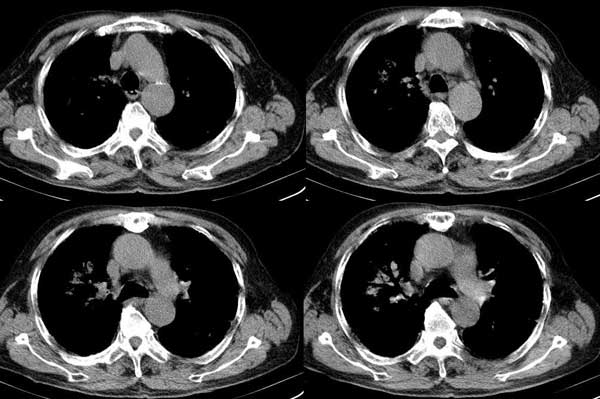

以下是引用dalianren在2006-7-20 21:23:00的发言:[br]我考虑是肺泡蛋白沉积症:典型表现为两肺内散在片状\"磨玻璃\"样混浊区呈地图样分布.

以下是引用lj0804在2006-7-21 12:57:00的发言:[br]支持[br]我考虑是肺泡蛋白沉积症:典型表现为两肺内散在片状\"磨玻璃\"样混浊去呈地图样分布.